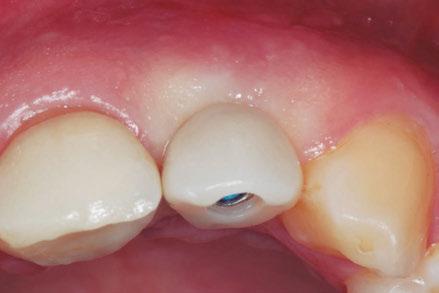

–Implante inmediato en incisivo lateral superior con técnica de «Socket Shield» y acceso vestibular para legrado de la lesión periapical, por el Dr. Ignacio Tormo Jiménez y cols. [106]